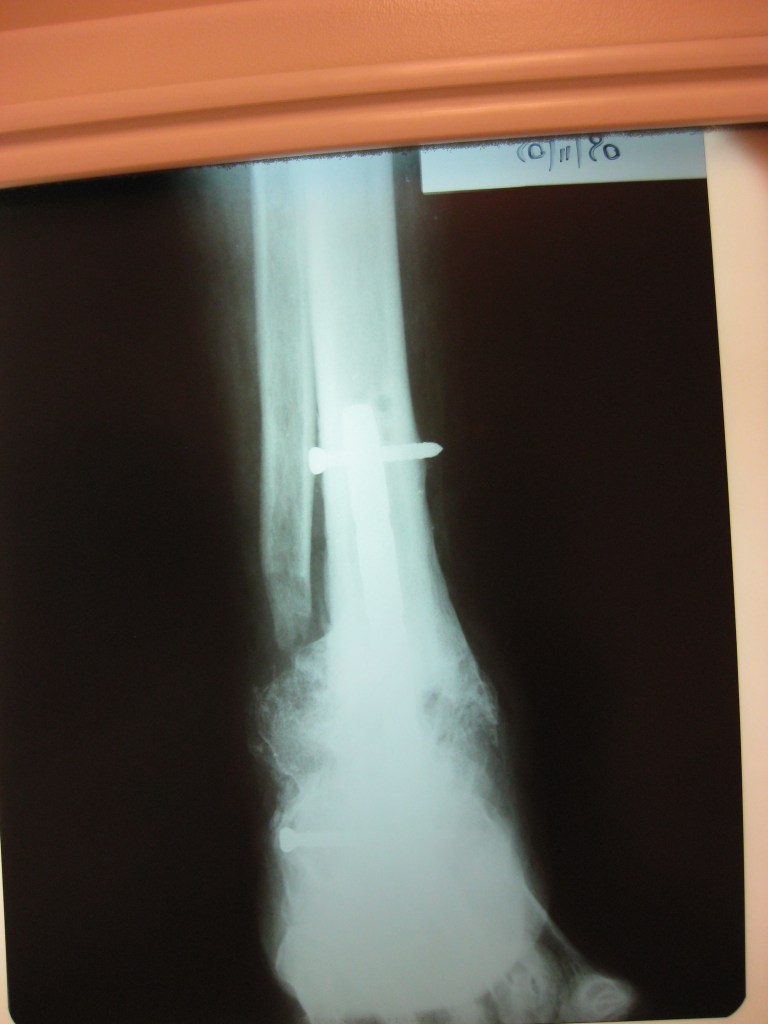

niño de 6 años con osmelitis en tibia

Luego de una fractura , mi hijo a los 6 años adquirió una infección ósea con exposición del hueso , que no podía tratarse en Chaco, por lo que tras una consulta con el Dr Dratewka , se explico las opciones de tratamiento

Luego de una 1 cirugía que consistió en remover todo el tejido muerto y acortar el hueso , pudimos tratar la infección ,y en una 2 cirugía alargar la pierna nuevamente